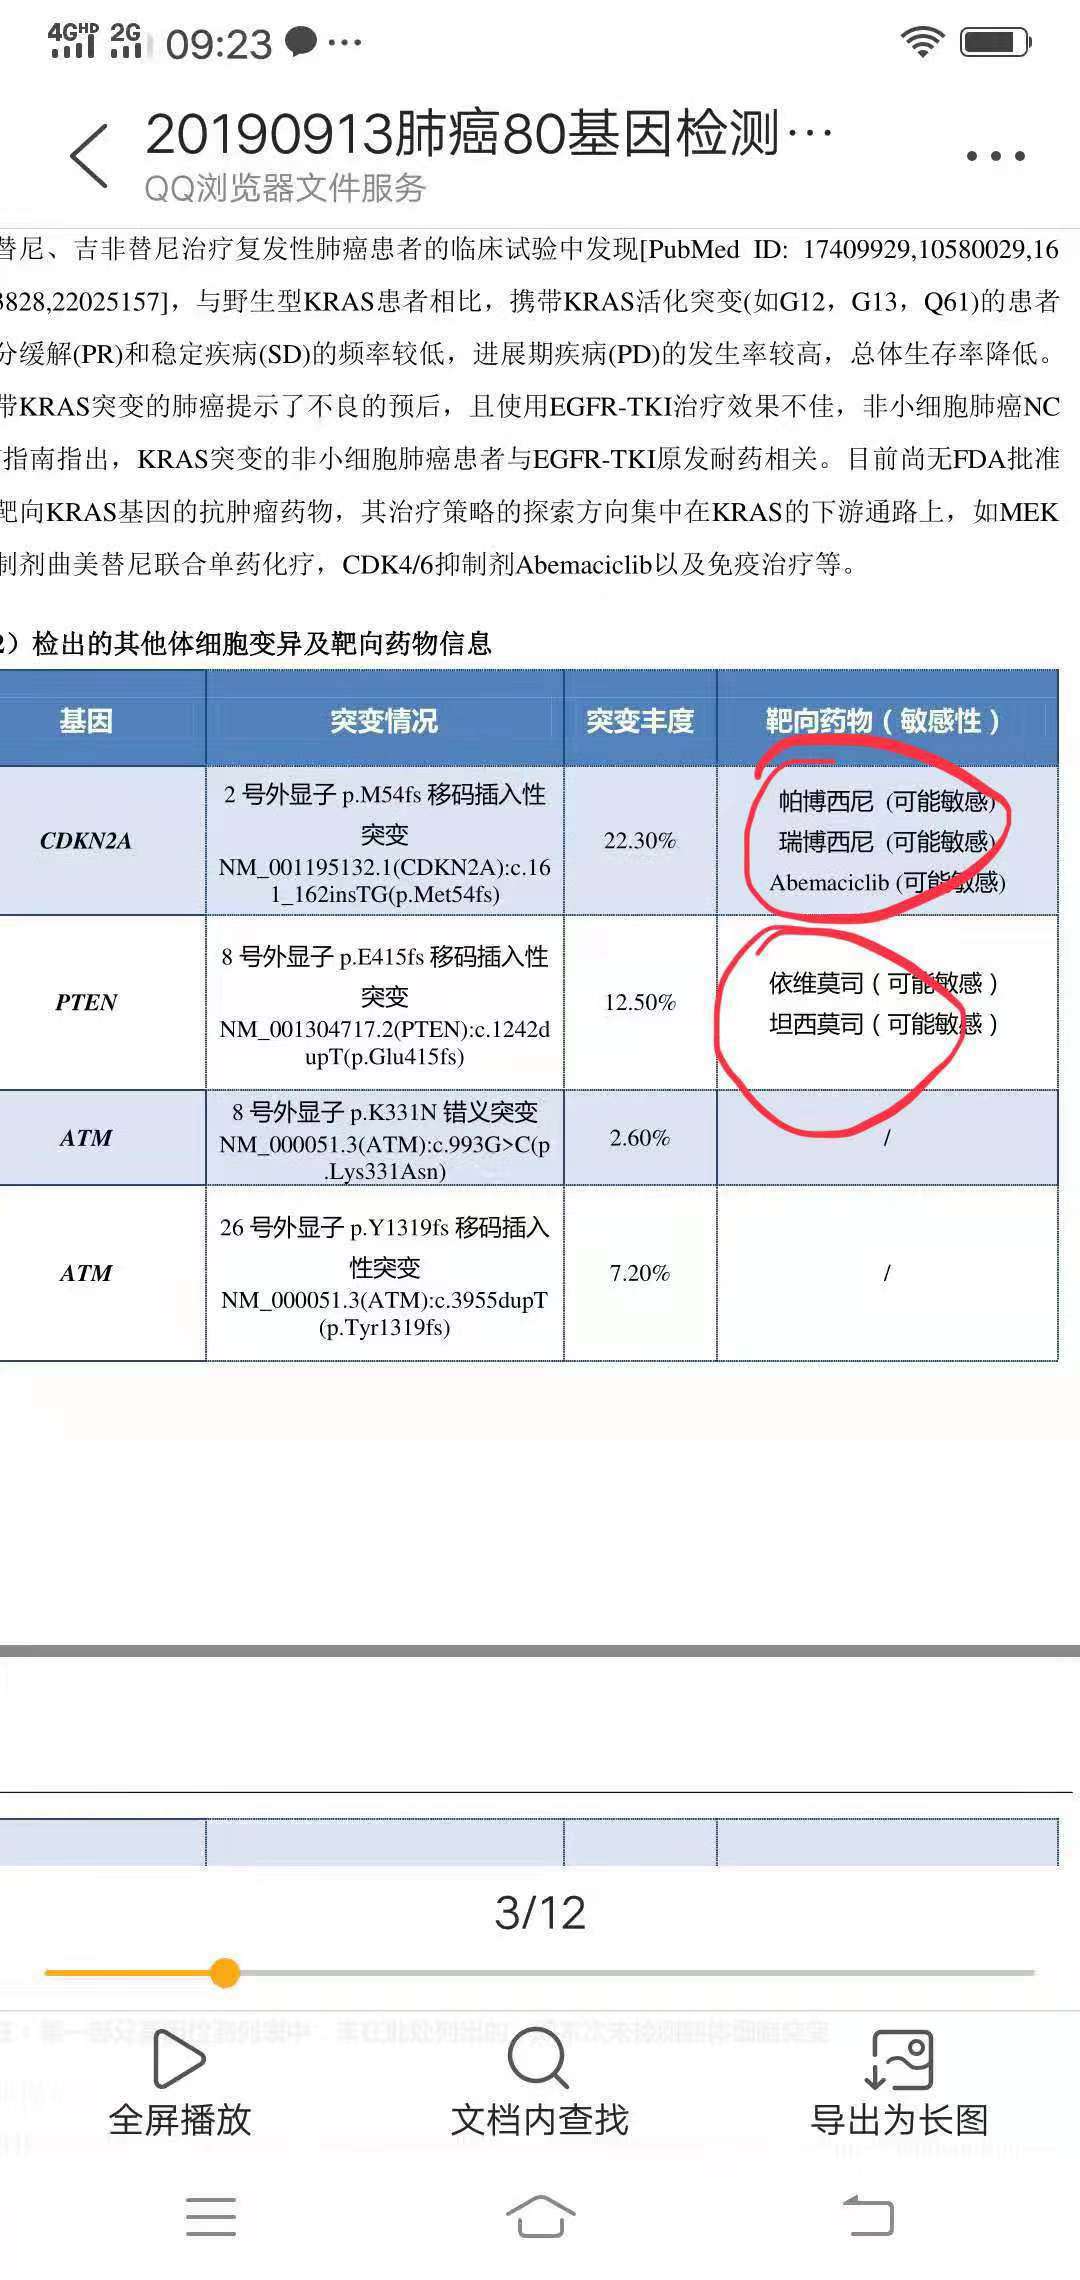

战战兢兢走过三年多点,这次复查有变化,化疗实在是不想再用了,老公身体状况很好和正常人一样,只是身体里有个不老实的总是反反复复折磨着人。16年5月份左肺下页手术,一年后复发,基因检测两次都是阴性,易瑞沙也盲试过无效 ,只能一直化疗,身体不耐受了就赶快停下来养精蓄锐,本来期待能老老实实的安稳两三年,哪想到复查七月份复查又有变化,盲吃了克唑替尼一个月也是无效。8月份右肺穿刺重新做检测,这次我们是幸运儿,有新突变但是不知道先用哪种好?

个人感觉按突变丰度高的基因用药好些。

CDKN2A和PTEN属于抑癌基因突变,KRAS是常见的原癌基因突变,前两者没有有效的靶向药,建议从KRAS入手,KRAS对化疗和免疫治疗敏感,已有的靶向药效果一般。